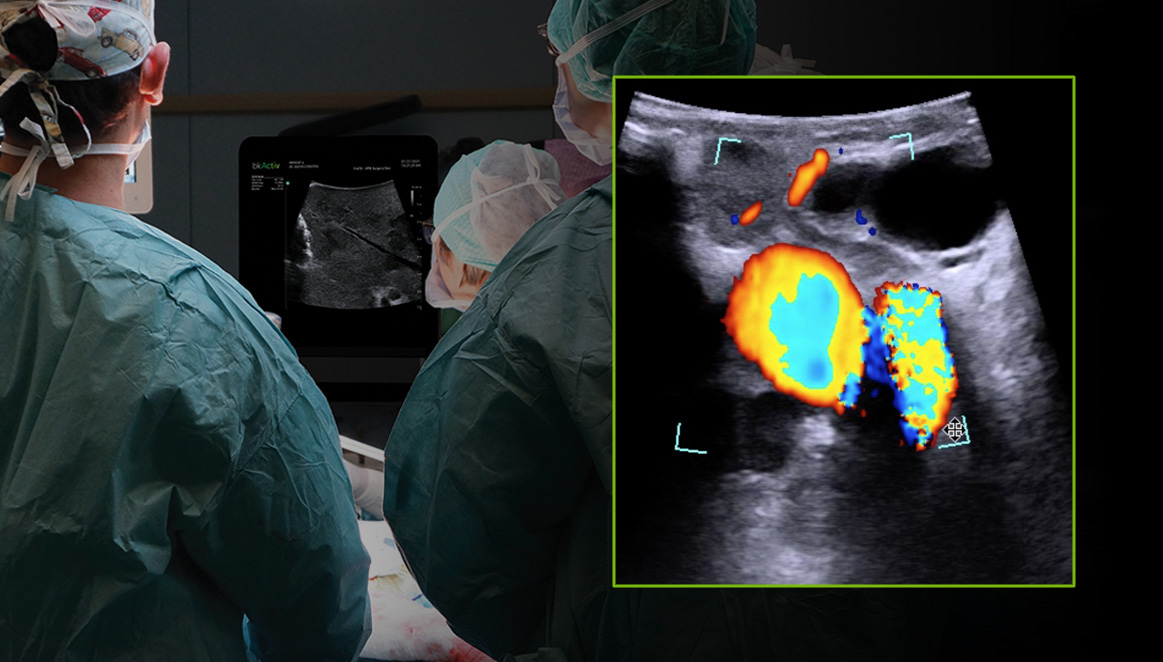

Discover the clinical benefits of active imaging with intraoperative ultrasound for laparoscopic cholecystectomy procedures. Using bkActiv and the Advanced Laparoscopic Transducer, surgeons can visualize anatomy and monitor progress as many times as needed during the procedure.

Bile Duct – Metastatic Tumor With Color Doppler

CASE STUDY

This case study walks through the steps of using intraoperative ultrasound in a laparoscopic cholecystectomy procedure performed by Mr. Somaiah Aroori, MB BS, MS (Surg), FRCS (Gen Surg), a consultant hepatobiliary and renal transplant surgeon at Derriford Hospital and University Hospital Plymouth in the UK. Throughout the procedure, bkActiv provided real-time information that cannot otherwise be obtained from preoperative imaging.